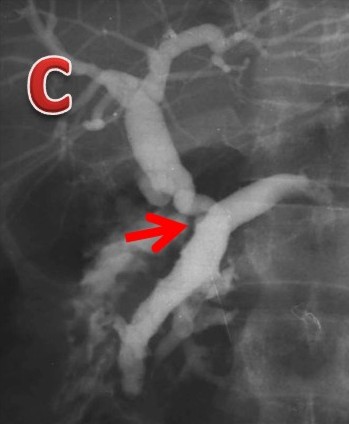

|

Figure 5. Tropical calcific pancreatitis. a. ERCP image showing a grossly dilated pancreatic duct with filling defects in the side branches and a dilated bile duct joining it in the pancreatic neck region (arrow) to form anomalous pancreaticobiliary ductal union of the B-P type. b. ERCP image showing a grossly dilated pancreatic duct with multiple large filling defects and the bile duct joining it in the body region (arrow) to form anomalous pancreaticobiliary ductal union of the B-P type. c. ERCP image showing a grossly dilated pancreatic duct with filling defects in the side branches and the bile duct joining it in the distal body region (arrow) to form a very long anomalous pancreaticobiliary ductal union of the B-P type. |